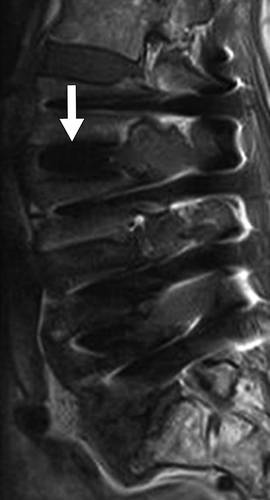

图13A-70岁的男性,在2年内进行数次腰椎手术,进行性疼痛。 骨扫描显示L2-L3间隙摄取量增加(未显示)。 血液检查显示C反应蛋白浓度和红细胞沉降率升高。矢状T2加权MR图像示出了L2-L3 椎间盘炎(箭头),合并L2-L3相邻终板和椎体破坏。 L2和L3椎体T2信号强度增高,表明水肿和梗死。